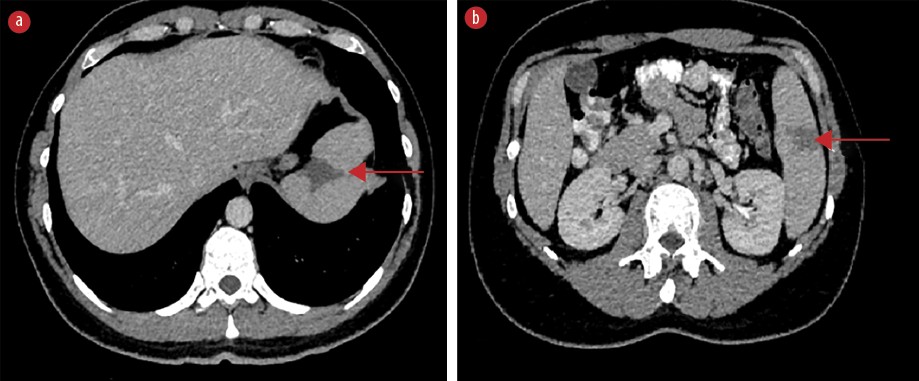

On the fifth day of hospitalization, the patient complained of new-onset left upper quadrant abdominal pain. Clinical examination revealed mild tenderness in the left upper quadrant and a palpable spleen. Computed tomography (CT) of the abdomen with intravenous contrast demonstrated multiple enlarged iliac lymph nodes, hepatomegaly (178 mm in the midclavicular line), and moderate splenomegaly (140 mm in the longitudinal axis). Multiple hypodense splenic lesions were visible without contrast enhancement, suggestive of splenic infarcts [Figures 1 and 2]. CT angiography of the abdomen showed no thrombi in the splenic vasculature. Hypercoagulability workup revealed mildly reduced protein S activity. Molecular testing for inherited thrombophilia (Factor V Leiden, Factor II-prothrombin, Factor XIII, MTHFR, and JAK2 V617 gene mutations) yielded negative results [Table 1]. Transesophageal echocardiography showed no evidence of thrombi, vegetation, or other abnormalities.

Figure 1: Axial contrast-enhanced CT scan demonstrating wedge-shaped hypodense splenic lesions without contrast enhancement indicative of splenic infarcts (red arrows), (a) located at the T10 level and at (b) the

L2 level.

Abdominal ultrasound is not recommended as the sole imaging modality because of its low sensitivity.6,9,14 The imaging modality of choice is contrast-enhanced CT, on which splenic infarcts commonly appear as wedge-shaped hypodense lesions without post-contrast enhancement after contrast administration.6,7 On magnetic resonance imaging, splenic infarcts are visualized as lesions with low signal intensity on both T1-weighted and T2-weighted images.9 In the present case, abnormal lesions suggestive of infarcts became evident on CT scan with intravenous contrast as wedge-shaped lesions without contrast enhancement.